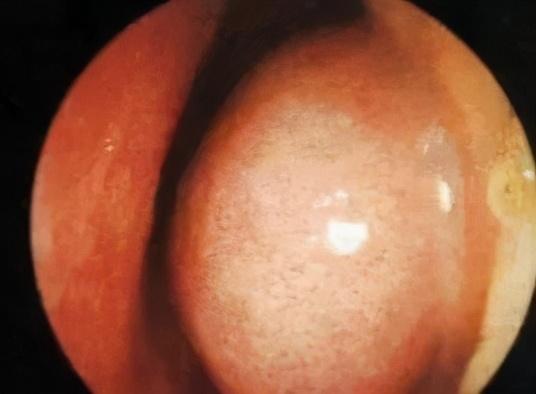

小贴士:如果不是因为分泌物过多,而是鼻粘膜水肿导致的鼻塞,可以去医院咨询医生,开一些局部喷剂,帮助缓解。

△鼻粘膜水肿图片

具体怎么判断呢?宝宝出现鼻塞时,可以用一个小手电(实在没有用手机灯也行),就能初步判断宝宝的鼻腔里是肿啦还是只是分泌物太多了。